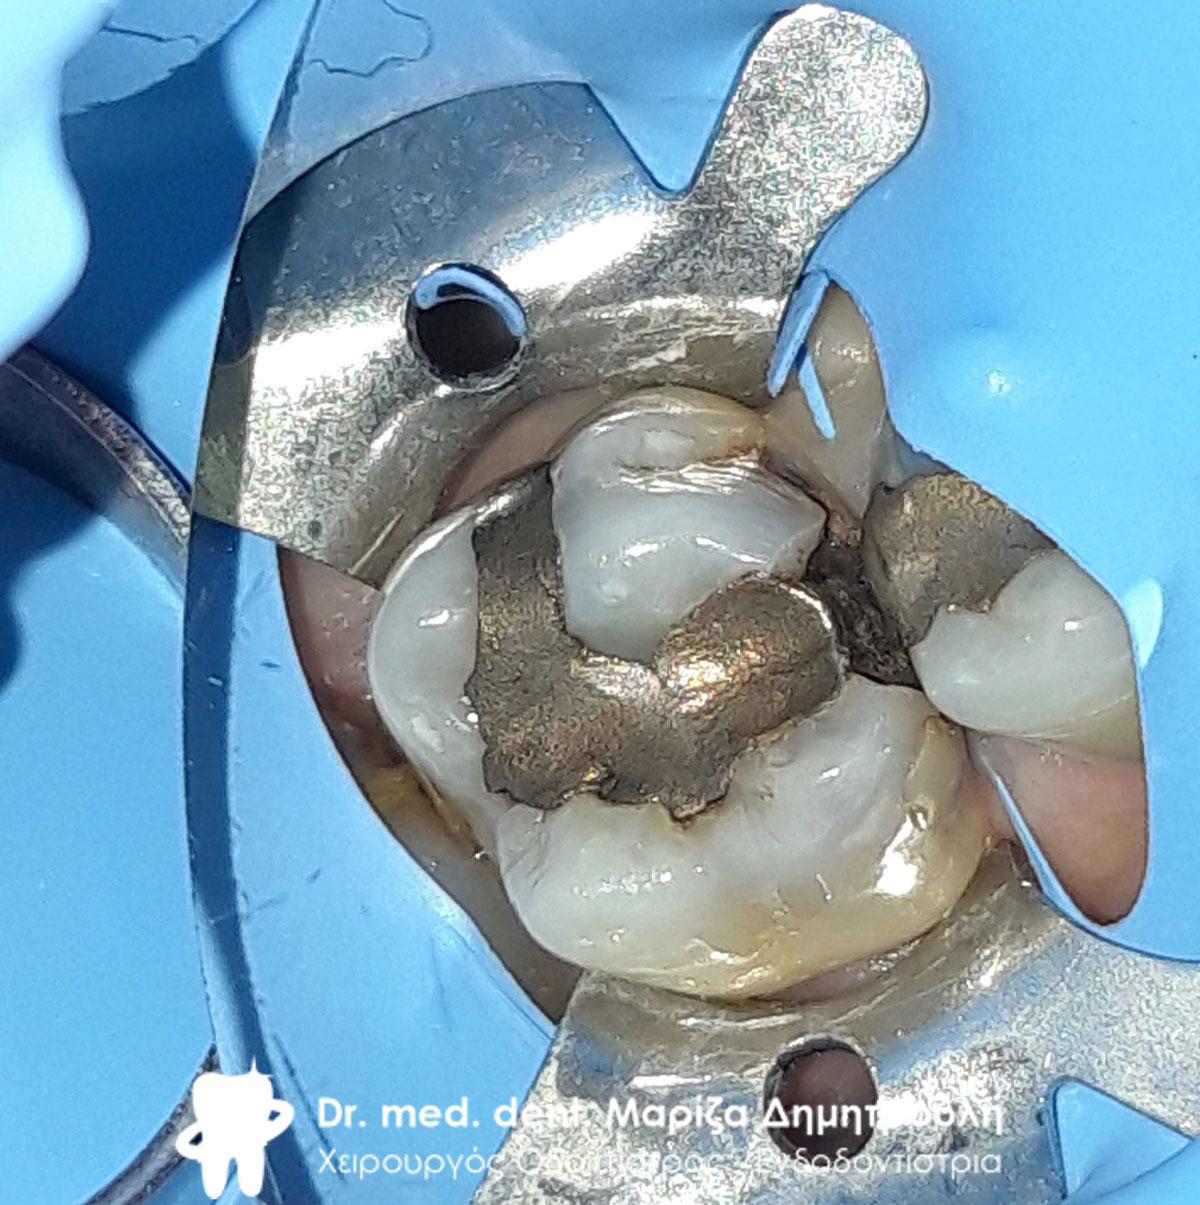

Εικόνα των τροχισμένων δοντιών με τις απαιτούμενες ανασυστάσεις

Εικόνα των τροχισμένων δοντιών με τις απαιτούμενες ανασυστάσεις

Κλινική εικόνα των κάτω δοντιών μετά τις απαραίτητες εργασίες

Ανασύσταση του πρώτου προγόμφιου και επανάληψη απονεύρωσης στο δεύτερο γομφίο

Ανασύσταση του πρώτου προγόμφιου και του δεύτερου γομφίου με λευκούς άξονες υαλονημάτων

Ανασύσταση του δεύτερου γομφίου και αρχική κλινική εικόνα του τρίτου γομφίου

Τελική εικόνα όλων των δοντιών πριν τη λήψη αποτυπωμάτων

Τελική εικόνα όλων των δοντιών πριν τη λήψη αποτυπωμάτων